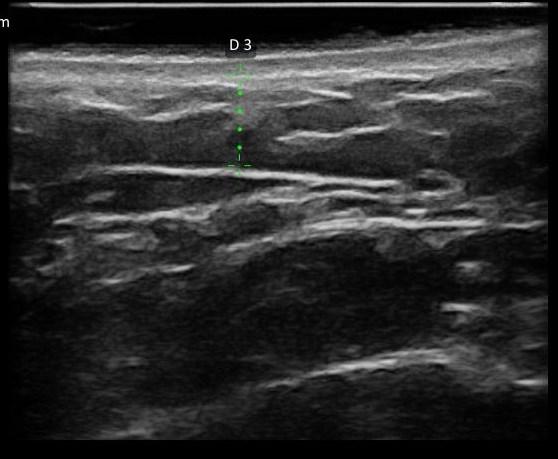

TECIDO SUBCUTÂNEO ANTES DO PROCEDIMENTO

TECIDO SUBCUTÂNEO DEPOIS DO PROCEDIMENTO